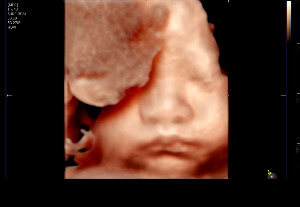

오늘은 찹쌀이의 얼굴을 가장 선명하게 볼 수 있는 마지막 입체 정밀 초음파가 있는 날이었다.

아내와 나는 이 날을 오래전부터 기다려왔다. 이전 정밀 초음파에서도 찹쌀이의 건강상태와

얼굴을 볼 수 있었지만 그때보다 쑥쑥 자란 만큼 출산 전 더 선명하게 찹쌀이의 얼굴을 볼 수

있는 날. 혹시나 검사를 하는 동안 잠들었을 경우를 대비해 초콜릿도 챙겨 입체 초음파실로

들어갔다. 담당 선생님은 밝은 목소리로 “오늘은 아기 얼굴이 잘 보이면 좋겠네요” 하며 초음파

검사를 준비했다. 우리는 그 말만으로도 벌써 가슴이 뛰었다.

그러나 막상 시작된 화면 속에서 찹쌀이는 좀처럼 얼굴을 보여주지 않았다.

양손을 얼굴에 가져다 대고, 몸을 돌려버리고, 아예 얼굴을 파묻고 있는 모습이었다.

마치 “아직은 안 보여줄 거야” 하듯 숨바꼭질을 즐기는 듯했다.

아내는 미리 챙겨 온 초콜릿을 꺼내 한입 먹으며 혹시나 찹쌀이가 움직여주길 바랐다.

선생님도 아내의 배를 살살 흔들며 “조금만 움직여줄래?” 하듯 유도했다.

그렇게 20분 넘게 시간을 들였지만 쉽게 모습을 드러내지 않았다.

그 순간, 잠깐 몸을 비트는 찰나에 화면에 얼굴이 정면으로 잡혔다. 작은 이목구비가 또렷하게

보였고, 통통하게 오른 볼살까지 그대로 담겼다. 그 한 장면을 얻기 위해 흘린 땀과 시간이 오히려

더 값지게 느껴졌다. 선생님이 사진을 저장해 주자 아내와 나는 동시에 웃음을 터뜨렸다.

KakaoTalk_20250921_205434255.jpg 20분간의 숨바꼭질 후 보여준 찹쌀이의 얼굴